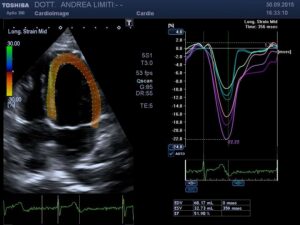

L’ecocardiografia è una metodica nella quale gli ultrasuoni sono utilizzati per visualizzare l’interno del cuore ed il flusso del sangue attraverso le valvole. A differenza delle radiazioni utilizzate in radiologia, gli ultrasuoni sono innocui, per cui non è necessaria alcuna precauzione e l’esame può essere eseguito su qualunque paziente innumerevoli volte (anche nelle donne in gravidanza).

Durante l’esame la sonda viene appoggiata al torace del paziente e gli ultrasuoni vengono diretti all’interno del corpo, senza che il paziente possa avvertirli. Gli ultrasuoni arrivano al cuore e ritornano alla sonda generando echi che sono utilizzati per visualizzare sullo schermo un cuore “virtuale” che ci informa del comportamento del cuore reale del paziente. Le onde sonore possono essere riflesse anche dal sangue in movimento all’interno del cuore e fornire informazioni sul flusso all’interno del cuore e dei vasi.

La visita cardiologica, l’Elettrocardiogramma e l’Ecocardiogramma bidimensionale Color Doppler transtoracico consentono di acquisire una ricchezza di informazioni sullo stato anatomico e funzionale del cuore di livello molto elevato che spesso consentono un primo accurato inquadramento dei problemi cardiologici del paziente. E’ importante tuttavia sapere che, anche con gli apparecchi più avanzati, l’ecocardiografia non offre una valutazione diretta dello stato delle coronarie e quindi l’esame non può essere discriminante per la valutazione di sospetti dolori cardiaci.